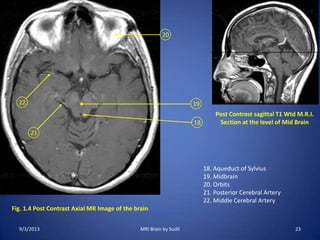

Fig. 1.9 Post Contrast Axial MR Image of the brain

Post Contrast sagittal T1 Wtd M.R.I.

Section above the Corpus Callosum

45. Parietal Lobe

46. Frontal Lobe